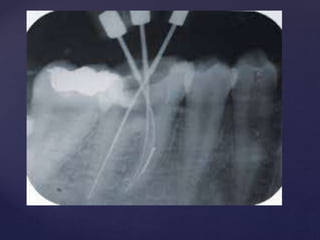

Apical Gauging

• The function of apical gauging is to measure the apical diameter of the canal

prior to cutting the final shape. This is necessary to ensure that the final tapered

preparation extends all the way to the terminus of the canal.

• Use NiTi K-files for gauging. The flexibility allows for much more accurate

apical gauging in curved canals than with stainless steel, insuring the apical

accuracy of obturation.

• No effort is made to cut dentin during apical gauging. The gauging

instruments are inserted straight in and are pulled straight out with no rotation.

• Always use 17% aqueous EDTA as an irrigant during gauging to remove the

smear layer.